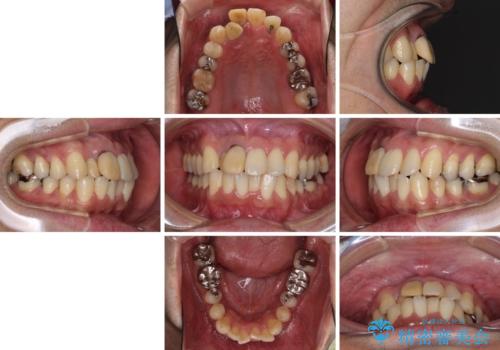

隠れている前歯 インビザライン矯正治療と前歯のセラミック治療

- 隠れるほどに内側に転位しいてる前歯を気にして来院された患者様です。

仕事柄海外出張が多いとのことで、インビザラインにて矯正治療を行うこととしました。

矯正治療後は、前歯や下顎の奥歯など、むし歯治療途中の歯をオールセラミッククラウンにて補綴治療を行うこととしました。

治療途中で海外に長期滞在することとなり、5年近く帰国することができなかったため、治療期間は非常に長いものとなりました。

内側に転位していた前歯は、矯正治療では治しきることができませんでしたが、幸いにもオールセラミッククラウンに置き換える予定であったため、希望通りの仕上がりとなりました。